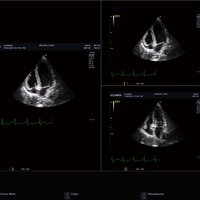

• Sektor/ Phased array-Sonden

• MP1-5X (1-5 MHz) für Ultraschalluntersuchungen in Bereichen Kardiologie, Abdomen, Pädiatrie, EM, TCD

• SP3-8T (3-8 MHz) für Ultraschalluntersuchungen in Bereichen Kardiologie, Abdomen, Pädiatrie, EM